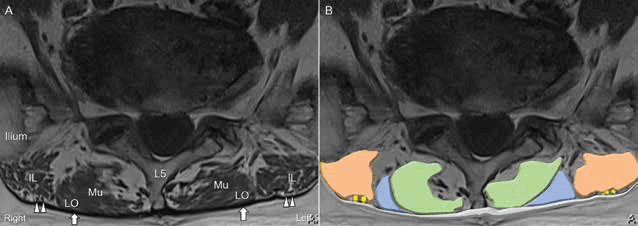

자기공명영상과 초음파 영상을 비교 분석하여 상둔신경 분지들의 위치를 정확히 파악했습니다. 수압박리술 - 그림 3. 자기공명영상(magnetic resonance imaging, MRI)(A)과 Figure 3. 그림 3. 자기공명영상(magnetic resonance imaging, MRI)(A)과 상둔신경 분지들에 대한 개략도(B)입니다.